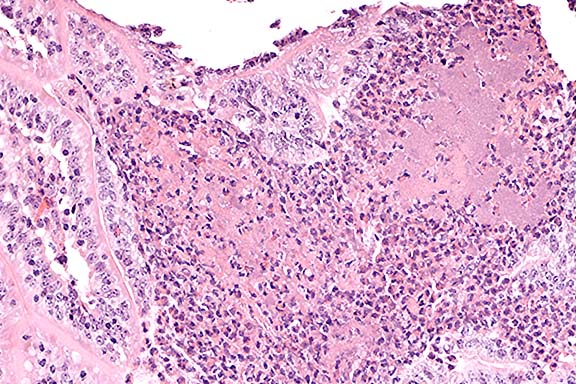

Case 23-1. Heart. Muscle necrosis and mineralization with mild fibroplasia, focal hemorrhage, and a moderate influx of lymphocytes. 20X

1. Myocardial necrosis and hemorrhage, focal, papillary muscle of heart.

2. Perivasculitis, nonsuppurative, heart and oral cavity.

The most consistent lesion of BT is focal hemorrhage in the tunica media at the base of the pulmonary artery.5 Hemorrhage and/or edema can also be seen in the pharynx, larynx, lungs, forestomachs, abomasum, kidneys, urinary bladder, gallbladder, urethra, vulva, or prepuce. Microscopic findings are characterized by microthrombi and infarction, along with neutrophilic infiltration (early lesions) or mononuclear reaction in uncomplicated chronic lesions. There is myocardial necrosis, most prominent in the papillary muscle of the left ventricle.5